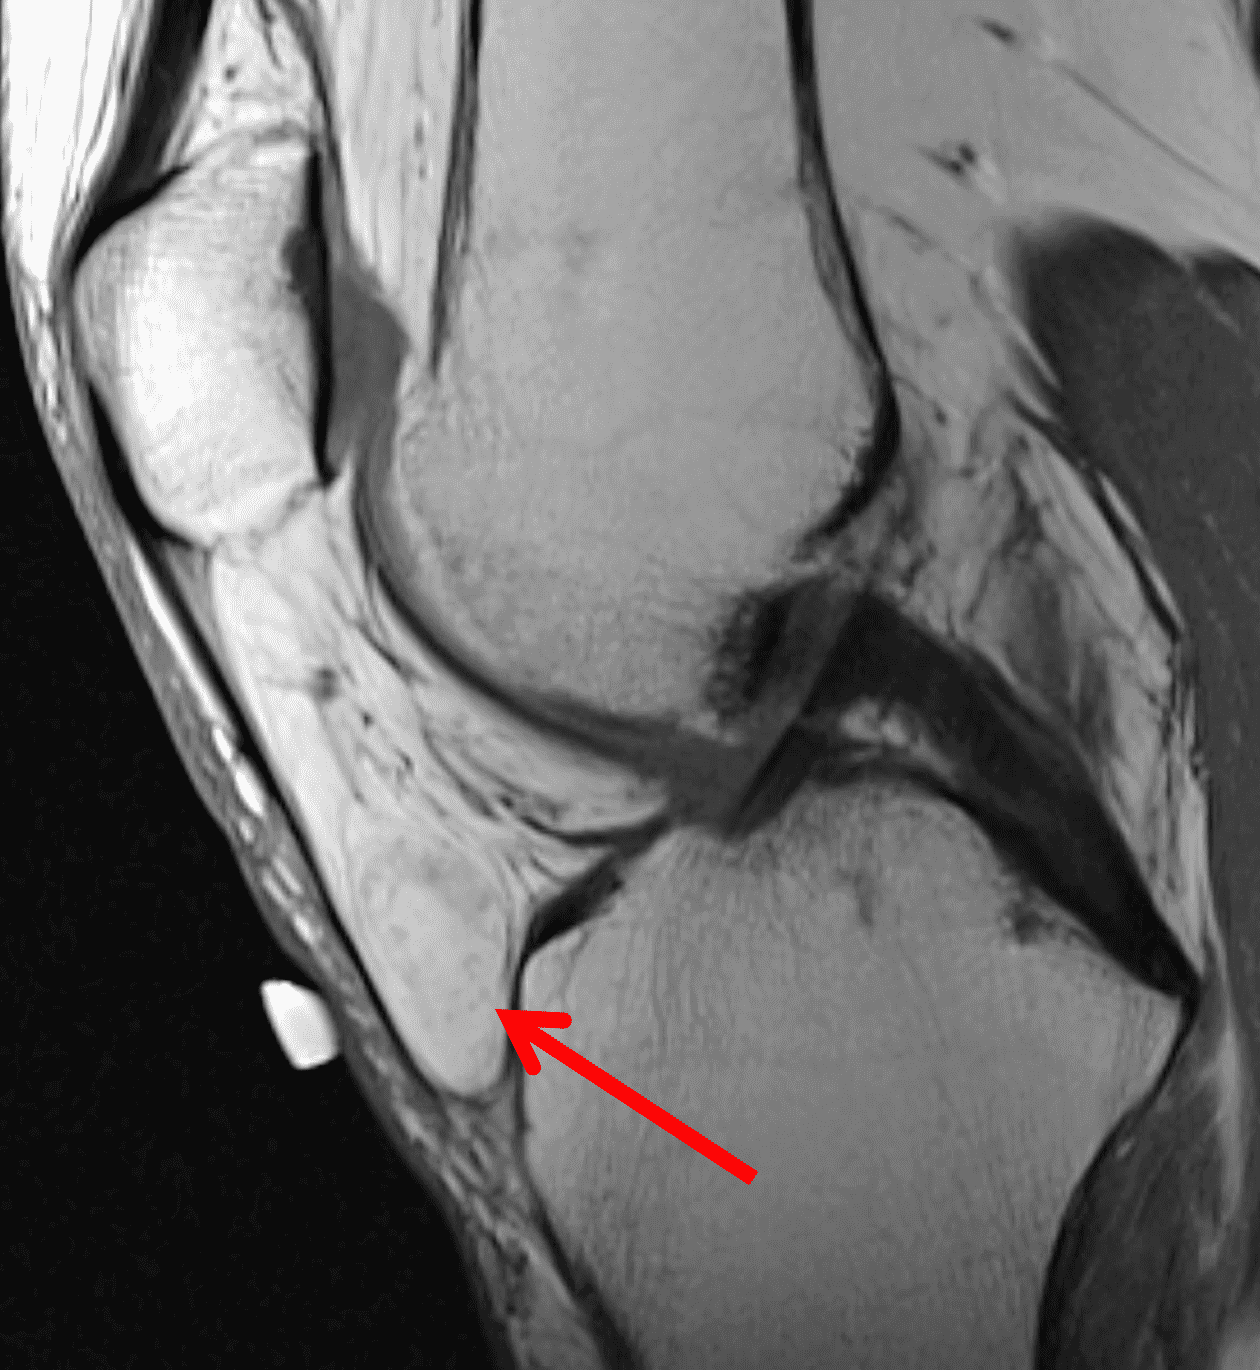

MRI demonstrates a well circumscribed, usually ovoid (sometimes multilobulated) intra-articular mass with nonspecific signal, usually intermediate to hyperintense T1 and variable T2 signal, with internal contrast enhancement due to capillary proliferation. Internal hypointense areas may be present, representing hemosiderin deposition and may demonstrate blooming artifact on gradient echo sequences. Internal linear T2 hyperintensity has also been described, possibly representing focal necrosis or fluid entrapment (Figure 16).1 Joint effusion is less common compared to the diffuse type.5

Figure 16: Localized type of tenosynovial giant cell tumor in two patients. Sagittal (16A) proton density-weighted and (16B) fat-suppressed fluid sensitive images of the knee demonstrate a circumscribed, intermediate T1 and T2 signal mass in Hoffa’s fat pad (asterisks), with areas of internal hypointensity representing hemosiderin deposition. In a second patient, axial (16C) T1-weighted and (16D) fat-suppressed fluid-sensitive images of the elbow demonstrate an anterior mass (asterisks) with the same signal intensity as well as characteristic curved hypointense foci within the lesion (arrows).